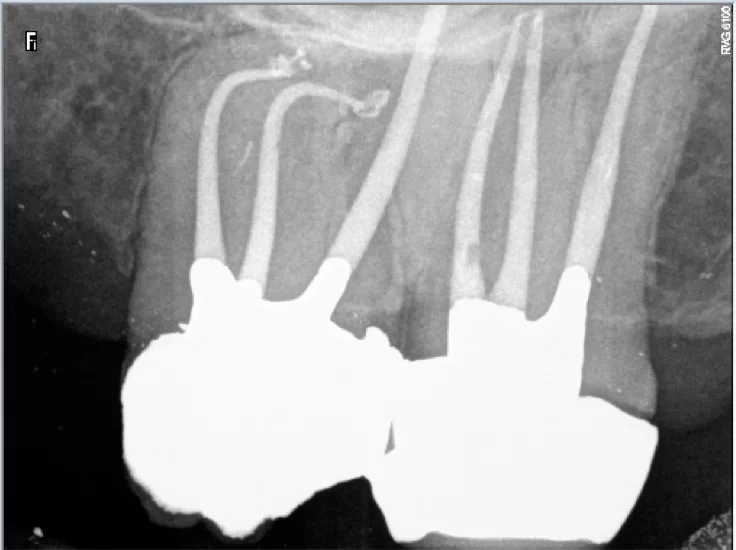

Η ενδοδοντική θεραπεία (απονεύρωση) σήμερα ολοκληρώνεται πλέον σε μία συνεδρία και αποτελείται από δύο στάδια ,τη χημικομηχανική επεξεργασία (καθαρισμό) των ριζών και την έμφραξη αυτών με τα κατάλληλα υλικά (γουταπέρκα και φύραμα).

Τόσο η επεξεργασία όσο και η έμφραξη των ριζικών σωλήνων χρειάζονται υψηλή ικανότητα ωστε να γίνουν γρήγορα και ατραυματικά ώστε να ελαχιστοποιηθούν τα συμπτώματα και να διασφαλισθεί η διατήρηση του αποτελέσματος στην πορεία των χρόνων. Η όλη διαδικασια είναι εντελώς ανώδυνη και τα αποτελέσματα πολύ ανώτερα από προηγούμενες γενιές καθώς ο εξοπλισμός και τα χρησιμοποιούμενα εργαλεία έχουν αναβαθμιστεί αρκετά την τελευταία δεκαετία.